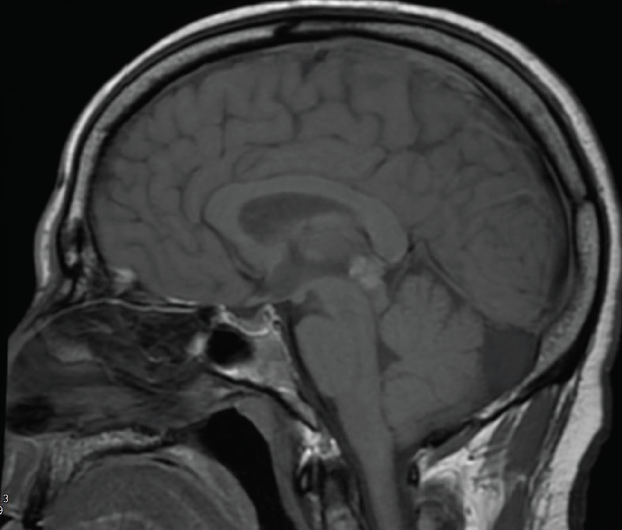

Diplopia What to Double Check in Radiographic Imaging of Double Vision Binocular Diplopia Sudden Onset When a person over 65 complains of monocular diplopia, the usual diagnosis is cataracts or dry eyes. The type of diplopia the patient complains of—horizontal, vertical or diagonal; pain, especially during eye movements, and redness may suggest orbital pathology from infection, inflammation, neoplasm,. Monocular diplopia is typically due to an ocular cause , while bilateral diplopia is more commonly. Binocular Diplopia Sudden Onset.